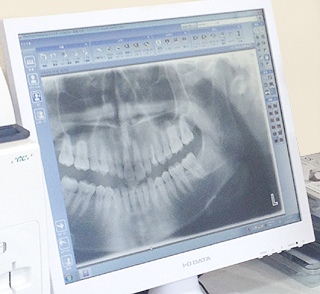

■デジタルレントゲン撮影装置

従来のX線撮影装置より、はるかに少ない照射量でより精密な画像診断ができます。

撮影した画像はすぐに見ることができ、現像の必要もありません。

画像を見ながら、悪くなった原因を分かりやすくご説明し

理解して頂いたうえで治療を開始します。